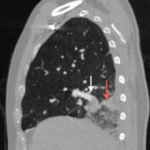

A 51-year old male presented to the emergency department with right chest and flank pain, with intermittent cough productive of blood-tinged sputum. The patient denied shortness of breath. The patient was afebrile, had a heart rate of 104/min, respiratory rate of 18/min, and oxygen saturation of 98% on room air. Cardiopulmonary exam was unremarkable. Chest radiograph (shown) was concerning for Hampton’s hump. Subsequently, the diagnosis of pulmonary embolism was confirmed on CT angiography of the chest (shown).

In the lateral view chest x-ray, there is a Hampton’s Hump, a pleural based, wedge-shaped opacity at the base of the right lung, representing lung infarction (black arrow). These findings correlate with the sagittal view on CT angiography of the chest. The CT chest also shows a filling defect in the distal posterior basal segmental pulmonary artery (white arrow), as demonstrated by the absence of contrast enhancement in the distal portion of the vessel. This is associated with an opacification of the lung parenchyma distal to the occlusion (red arrow), representing lung infarction.

The diagnosis of pulmonary embolism is typically made by CT pulmonary angiography, but other diagnostic modalities include: ventilation-perfusion scan, d-dimer, ultrasound of the lower extremities, echocardiogram, electrocardiogram, chest radiograph, and clinical decision rules. Hampton’s hump (figure 1), a wedge-shaped consolidation with the base of the triangle against the pleura, was first described on the chest x-ray in the 1940s and is one finding that may be present on chest radiography.1-3

The presence of Hampton’s hump possesses a high specificity (82%), but has a low sensitivity (22%) for the diagnosis of pulmonary embolism.3,4 In patients with Hampton’s hump, CTA will confirm the diagnosis, showing a three-dimensional infarction distal to the embolus.